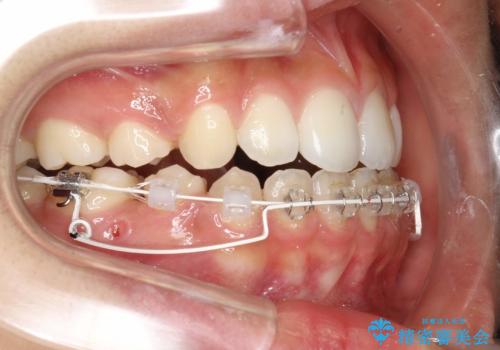

- 審美装置

- 2年3ヶ月

- 10-30回

- 約95万円費用は治療当時の料金となります

口元を下げて口唇を閉じやすくする場合、抜歯矯正をお勧めさせていただくことが多いです。